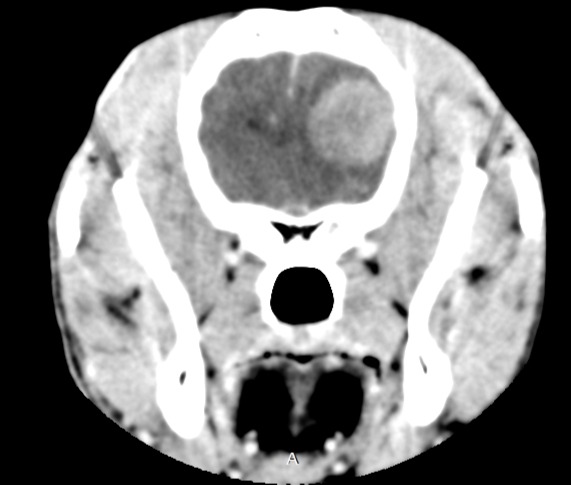

Imagerie médicale

L’imagerie médicale est une discipline transversale nécessaire au dignostic dans de nombreuses pathologies tant en médecine spécialisée, qu’en cardiologie, en neurologie ou en chirurgie.

Neurologie

L’atteinte du système nerveux est difficile à évaluer car les symptômes peuvent être subtiles. La neurologie vétérinaire s’intéresse à l’étude, au diagnostic et au traitement des affections du système nerveux (cerveau, moelle épinière, nerfs périphériques).